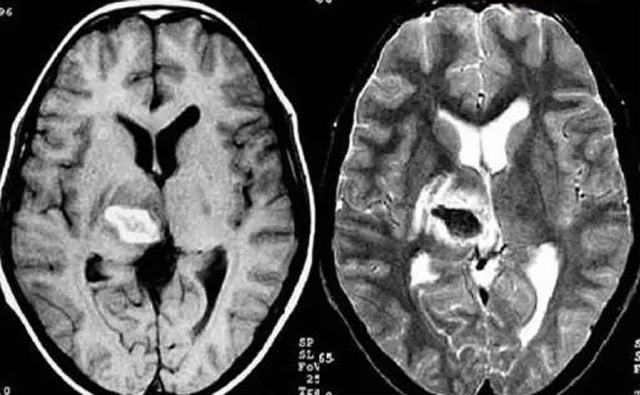

發(fā)現(xiàn)病人出血腦梗相關(guān)癥狀時候第一時間就醫(yī),需要攜帶以往的影像檢查資料。向醫(yī)生提供相關(guān)的病史基本資料。做影像檢查時候需要全身不攜帶金屬物品。檢查時候身體保持不動,不然偽影對檢查結(jié)果有干擾。磁共振MRI發(fā)現(xiàn)缺血性卒中后,幫助進一步查找病因。由于CT上小腦跟腦干顱骨影響,容易導(dǎo)致漏診。MRI檢查可以對CT檢查不足的補充。短暫的腦缺血TIA也需要進行影像檢查。短暫性缺血一般10幾分鐘后好轉(zhuǎn)。檢查目的可以確定TIA的病因。降低腦梗死的發(fā)生率。磁共振有助于排出TIA表現(xiàn)的顱內(nèi)病變,有診斷及時治療的價值。磁共振MRI檢查時間比較長,不太適合急診病人。但是可以發(fā)現(xiàn)腦干小腦的出血問題。因為急性腦梗死的早期和急性期,缺血區(qū)的腦組織還沒有完全壞死,頭顱CT不能顯示病灶,所以就需要MRI磁共振檢查,這個對陳舊跟亞急性出血顯示比較好。缺點性價比不高,費用比較貴。頭顱的磁共振MRI在發(fā)病后的幾天CT的敏感降低時候發(fā)揮大作用。,MRI可作為診斷蛛網(wǎng)膜下腔出血和了解破裂動脈瘤部位的一種重要方法,必要時進一步進行DSA檢查,幫助制訂臨床的手術(shù)治療方案,

經(jīng)顱多普勒超聲(TCD)有效沒有創(chuàng)傷性的檢查方法,是檢查腦血管的設(shè)備之一,它目前廣泛應(yīng)用于臨床,檢查判斷腦出血卒中的頭顱里面的內(nèi)動脈外動脈的病變問題。診斷顱內(nèi)動脈狹窄或閉塞性病變。顱外頸部動脈狹窄或閉塞性病變,評價顱外動脈嚴(yán)重狹窄或閉塞對顱內(nèi)血流速度的影響。頸動脈內(nèi)膜剝脫手術(shù)前預(yù)測夾閉作用、術(shù)后評估顱內(nèi)血流變化。